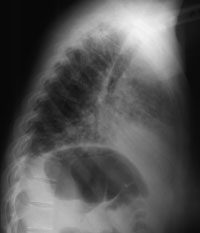

Please look at the chest X-rays.

Enlarge RIGHT IMAGE / Enlarge LEFT IMAGE

WHAT IS YOUR RADIOLOGICAL DESCRIPTION ?